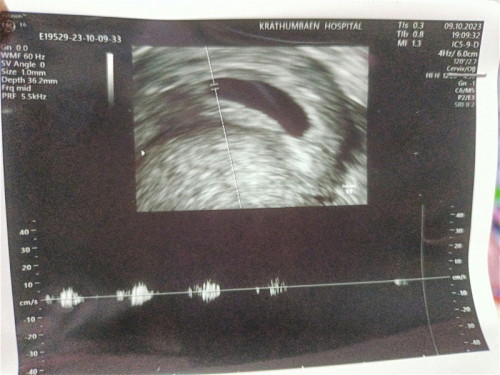

หลังจากที่ไปซาวด์มาตอน4วีคไม่เจอถุงตั้งครรภ์ วันนี้ไปซาวด์ใหม่6วีค5วัน ซาวด์ผ่านช่องคลอดเจอน้องพร้อมเสียงหัวใจและถุงไข่แดง หนูยังตัวเล็กมากๆ แม่ดีใจมากๆลูก หนูต้องเกาะแม่แน่นๆนะรอบนี้